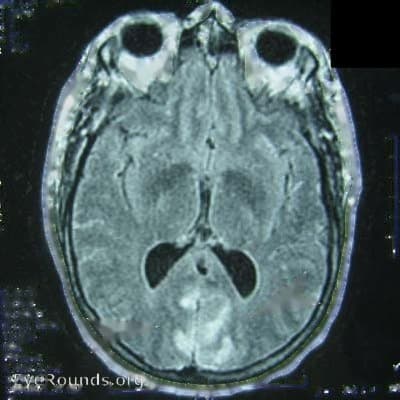

Clinical Images

High-resolution clinical photographs showing various presentations of optic neuritis.

An MRI of the brain helps determine your risk of developing Multiple Sclerosis.